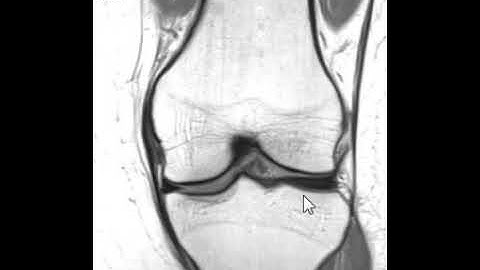

How to read a knee MRI?